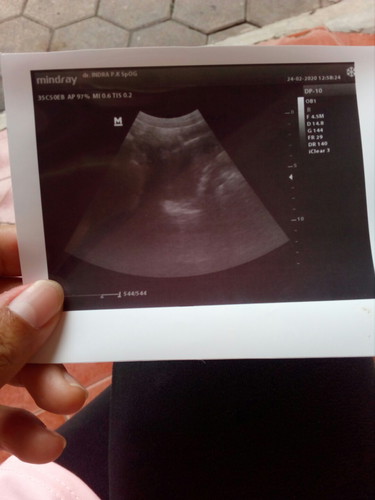

6 minggu blom kelihatan janinnya ?cuma kantungnya aja

Pada usia kehamilan 6 minggu masih sangat muda untuk melihat janin bun. Wajar jika yang terlihat hanya kantungnya saja. Jangan berkecil hati ya bun, bunda bisa usg lagi jika usia kandungan sudah lebih besar. Tetap semangat bunda π

Gpp... wajar ko bund... Nnti klo udh 8w.. usg lagi aja...